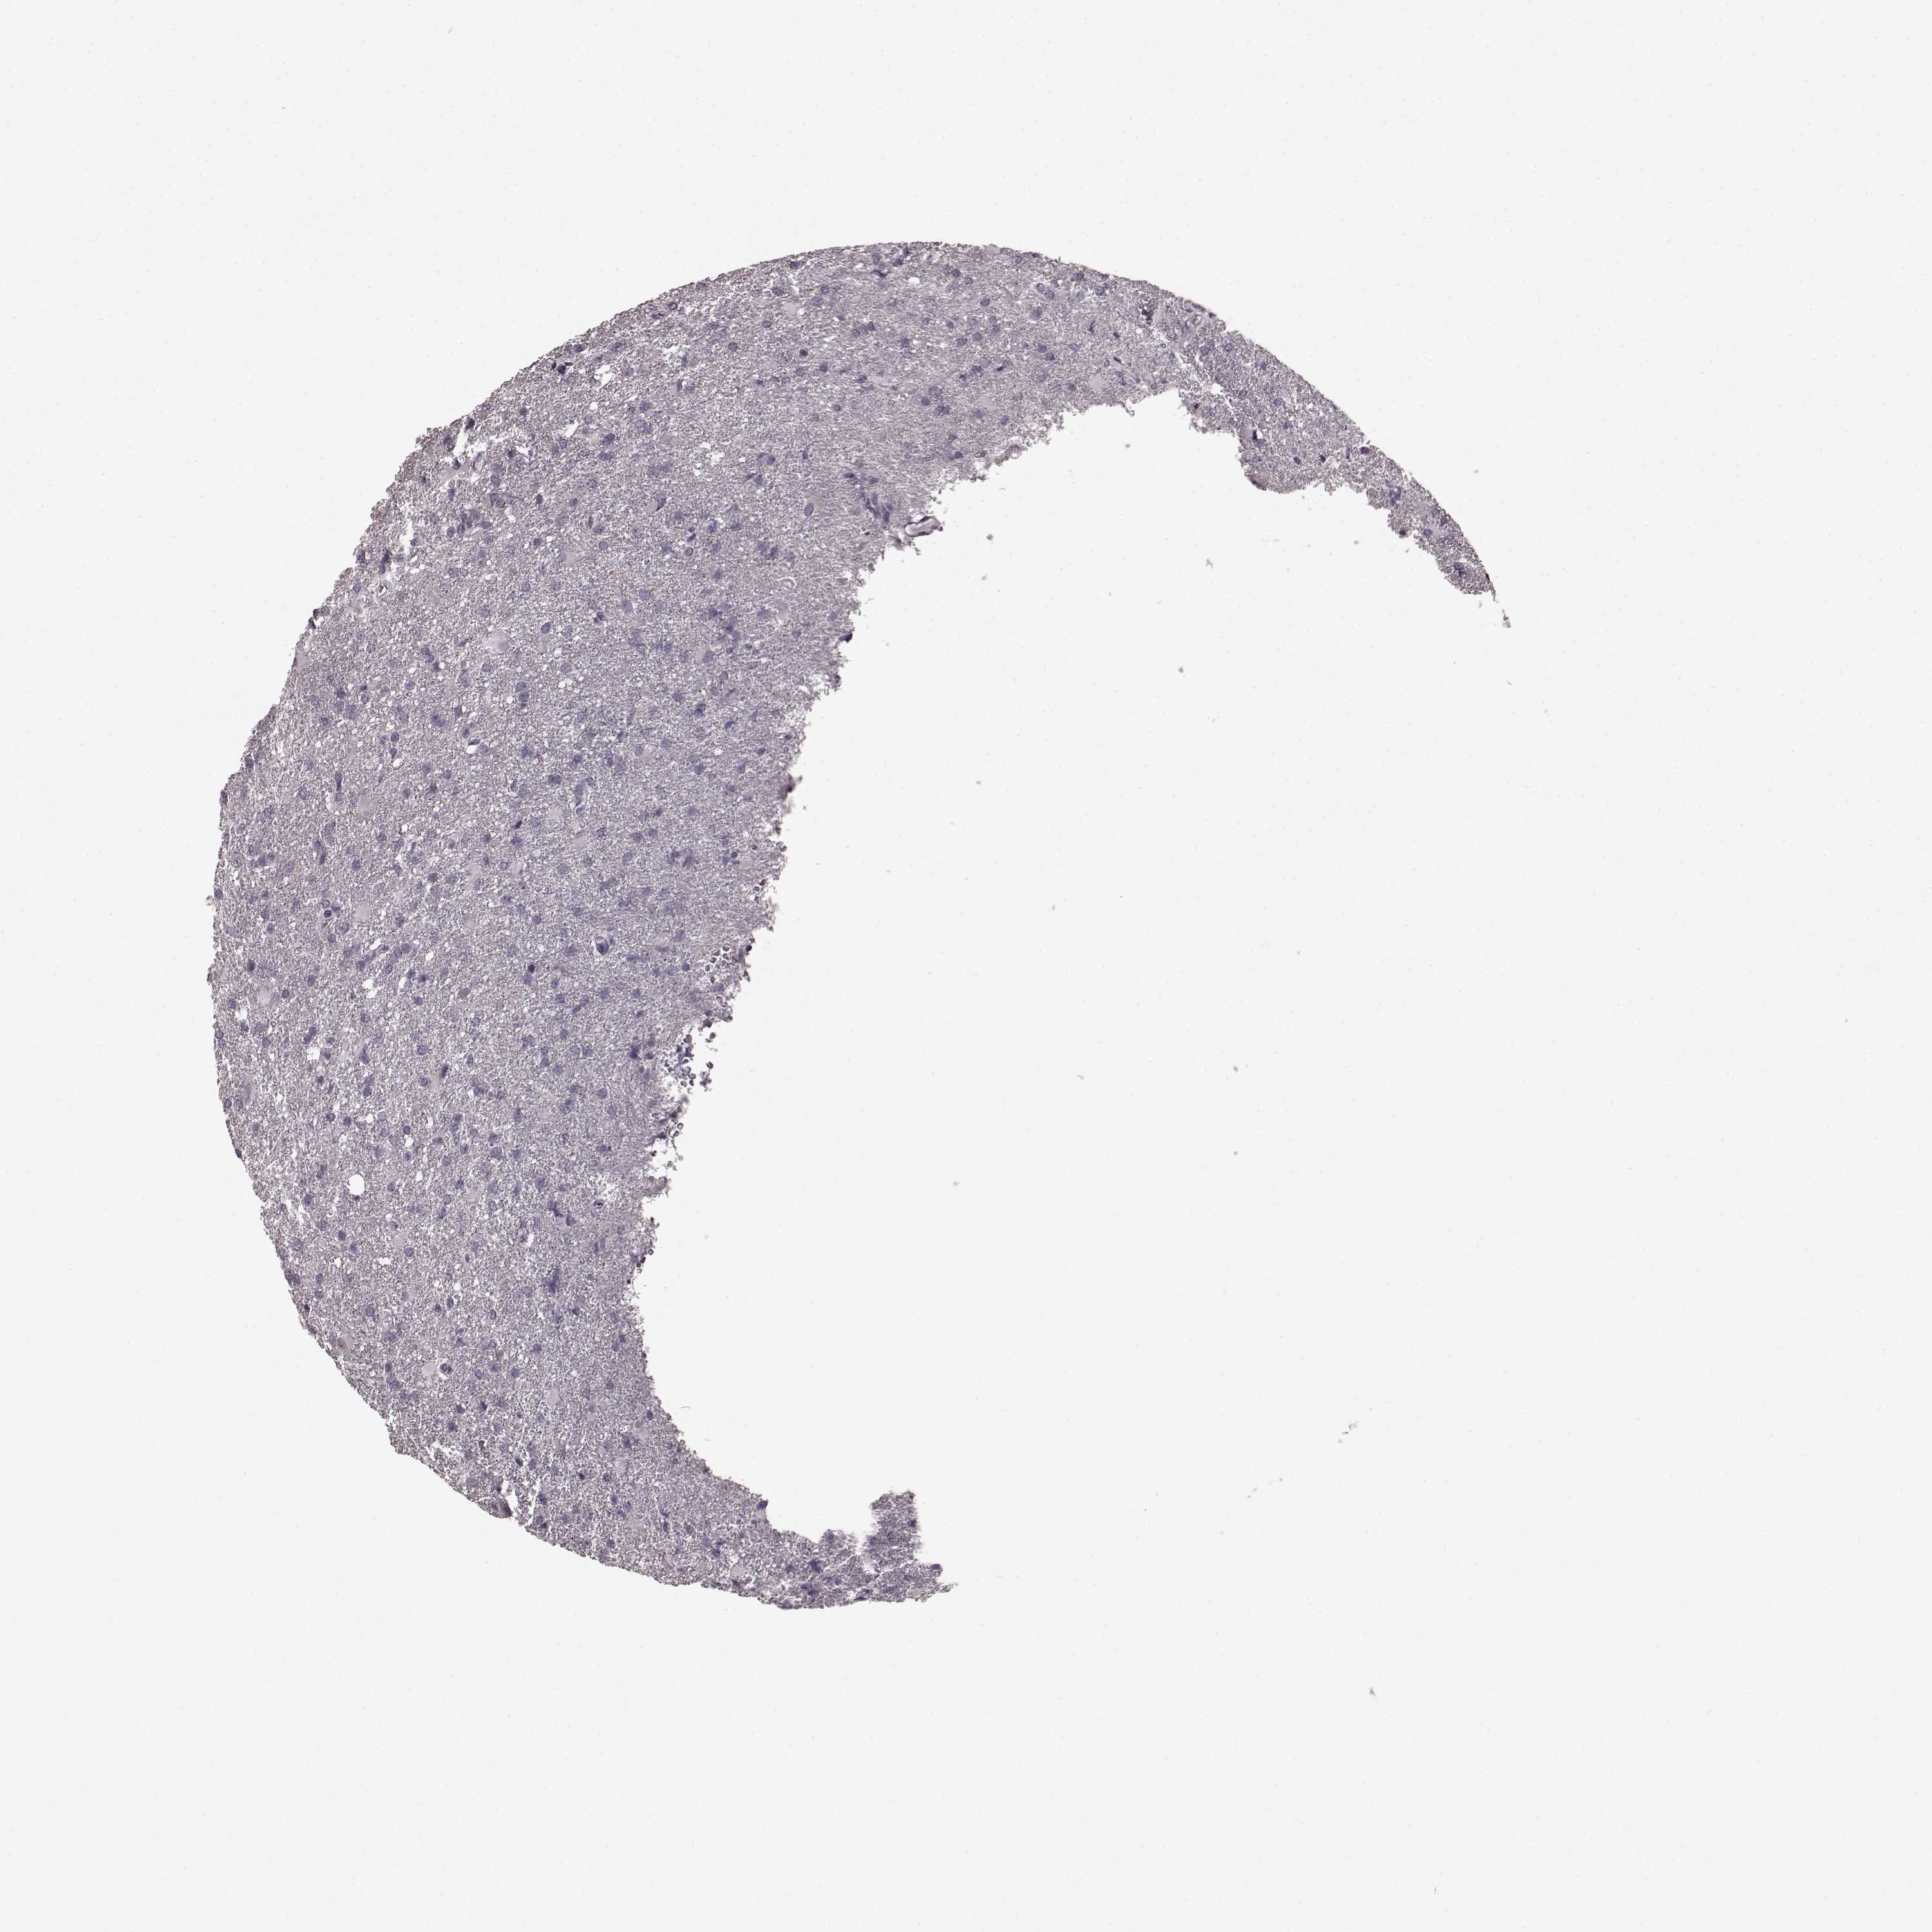

GLIOMA - Protein expressioni

A mouse-over function shows sample information and annotation data. Click on an image to view it in a full screen mode. Samples can be filtered based on level of antibody staining by selecting one or several of the following categories: high, medium, low and not detected. The assay and annotation is described here.

Note that samples used for immunohistochemistry by the Human Protein Atlas do not correspond to samples in the TCGA dataset.

Antibody stainingi

Antibody staining in the annotated cell types in the current human tissue is reported as not detected, low, medium, or high, based on conventional immunohistochemistry profiling in selected tissues. This score is based on the combination of the staining intensity and fraction of stained cells.

Each image is clickable and will lead to virtual microscopy that enables deeper exploration of all samples and also displays staining intensity scores, fraction scores and subcellular localization as well as patient and tissue information for each sample.

Antibody HPA070003

Staining

High

Medium

Low

Not detected

Intensity

Strong

Moderate

Weak

Negative

Quantity

>75%

75%-25%

<25%

None

Location

Nuclear

Cytoplasmic/membranous

Cytoplasmic/membranous,nuclear

Glioma, malignant, Low grade

Glioma, malignant, High grade

Glioma, malignant, NOS